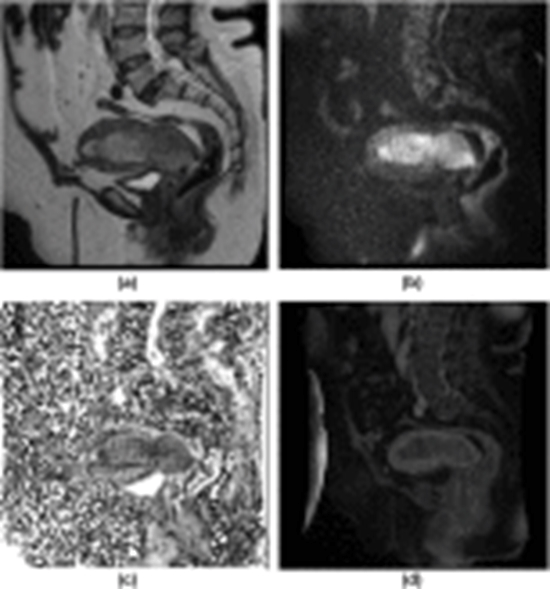

Advanced MRI prediction model for anatomical site identification in uterine carcinoma: enhancing diagnostic accuracy

Aim: The uterine carcinoma is the most commonly diagnosed malignancy in the female pelvis. Accurate identification of tumour origin is crucial for determining appropriate treatment approaches. This study aims to develop a prediction model using multiple MRI parameters to accurately diagnose uterine cancer with an indistinctive origin and those involving both the endometrium and cervix prior to treatment.

Results: A total of 78 patients with uterine carcinoma were enrolled. Certain imaging features were found to be consistent with cervical carcinoma, included parametrial, vaginal, stromal invasion, and peripheral rim enhancement. Cervical cancer appeared hyperintense compared to the myometrium unlike endometrial cancer.

Discussion: The study found that certain morphologic features were reliable indicators for detecting cervical carcinoma.